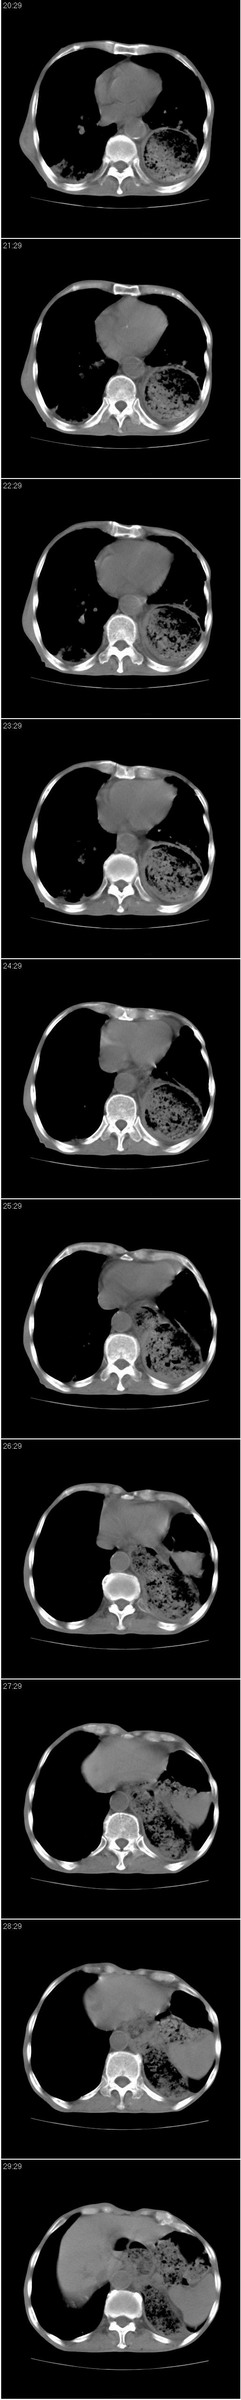

以下是引用andymaomao在2007-8-18 14:29:00的发言:[br][br]1.该患者应有食道ca手术史,胃位于左侧胸腔(后纵膈旁);[br]2.双肺继发性肺tb?!不排除部分病灶改变为转移灶;[br]3.纵隔气管旁可见肿大淋巴结;[br]4.右下侧后胸壁轻度增厚、粘连。[br]5.另左肺部分肺组织含气不良(受压!?)。[br][br]

以下是引用dyqct在2007-8-18 14:40:00的发言:[br]考虑:1、食道弓上吻合术后(左侧胸腔胃);[br] 2、右上继发型肺结核;[br] 3、慢性支气管炎合并全小叶型肺气肿、感染。